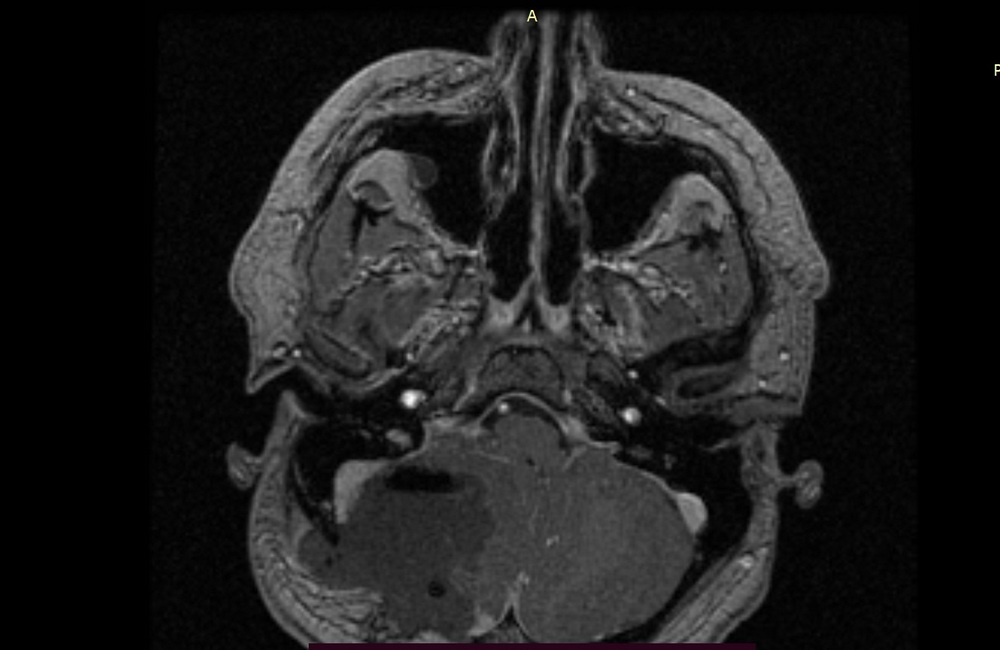

| Снимки до операции. Опухоль полушария мозжечка | Снимки МРТ послеоперационный контроль. Опухоль удалена полностью |

Благодаря применению этого подхода удалось полностью удалить опухолевые клетки не только в зоне операции, но и в прилежащих структурах головного мозга, что, в свою очередь, будет способствовать увеличению безрецедивного периода и улучшению качества жизни пациента. Послеоперационный период прошел без осложнений. На контрольных МРТ-исследованиях подтверждено тотальное удаление злокачественной опухоли головного мозга. Пациент выписан в удовлетворительном состоянии без неврологического дефицита.